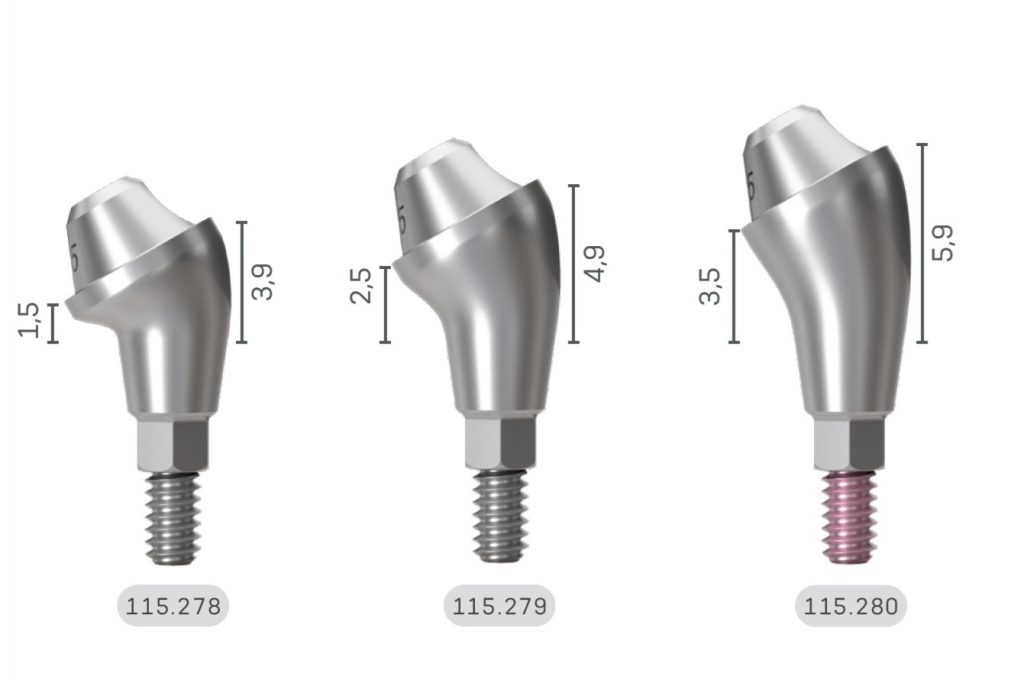

Да бих уштедео време, навешћу све неопходне карактеристике које систем имплантата треба да има у погледу повезивања:

- Унутрашњи – ово је постало очигледно давно. Спољна веза могла је бити дозвољена само изнад нивоа кости.

- Конусни – За лакше прилагођавање, боље заптивљење и равномерну расподелу оптерећења.

- Прелазак између платформи – Ово је деценијама очигледно, а ипак још увек постоје брендови који имају утапливени спој веза. Зашто је то, то ми је непојмљиво.

- Дубоко – Мислим да је само по себи објашњено. Плитке везе су мање стабилне и склоне опуштању вијака.

- Свестраност абатмента – Не само за различите типове рестаурација, већ и за различите висине десни. Сви абатменти морају поштовати биологију и пратити Правила профила емергенције – конкавно апикално, а затим конвексно коронално.

Све ово обезбеђује да абатмент је хладно заварено у имплантат, стварајући биолошко запечаћивање, јункционални епител који ће штитити кост и сва периимплантна ткива.